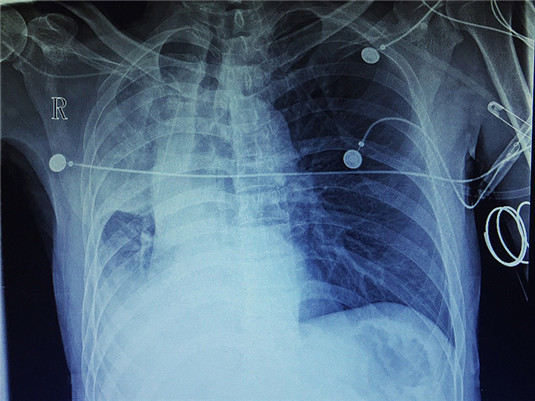

近日,一名胃穿孔、腹膜炎患者,急诊手术后出现呼吸困难转入东方医院重症医学科。入科时患者呼吸急促,大汗,口唇、四肢末梢紫绀,监测末梢血氧饱和度70%左右,血气分析提示1型呼吸衰竭,听诊双肺大量湿罗音,右肺呼吸音较左肺明显减低。

气管插管、呼吸机辅助呼吸,心电监护……抢救迅速展开,与死神的赛跑,争分夺秒,决不允许观望与等待,可是应用呼吸机后患者的指脉氧饱和度仍无上升,什么情况?我在脑海里迅速回放患者的诊疗经过,不放过每一个细节:双肺大量湿罗音、右肺呼吸音较左肺明显减低、插管时气道内未见痰液……难道是……痰液阻塞!?立即行床旁胸片检查,结果回示:右肺大片状密度增高影、肺不张。检查结果进一步印证了自己的判断。

患者病情已不允许有半刻迟疑,主治医师郭帮卫立即给予纤维支气管镜检查,镜下见右主支气管痰液阻塞,给予肺泡灌洗,随后从气道内吸出大量痰液,指脉氧饱和度逐渐上至95%以上,复查血气分析呼吸衰竭改善,复查胸片右肺复张,患者转危为安。